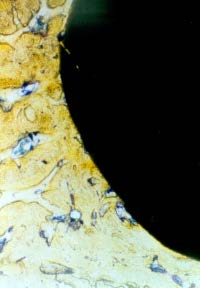

Two patients were administered antibiotics for postoperative infections, one starting on the 2nd postoperative day and the other starting on the 6th postoperative day. All patients showed complete radiographic healing/bone fill at their recall appointments, which ranged from 4 months to 72 months (median 29 months; mode 30.2 months). [See Figures 1 through 4. Figure 1: preoperative #31 X ray showing periapial radiographic lesion. Figure 2: 5-month postoperative Xray #31 showing complete radiographic healing. Figure 3: #30 preoperative X ray showing periapical radiographic lesion, Figure 4: #30 48-month postoperative X ray showing complete radiographic healing.] In addition, two patients (a 24-year-old two days after #30 was extracted and a 62-year-old six days after #31 was extracted) were seen for postoperative fibrinolytic alveolitis and possible infections were prescribed amoxicillin 500 mg three times a day for 6 days.